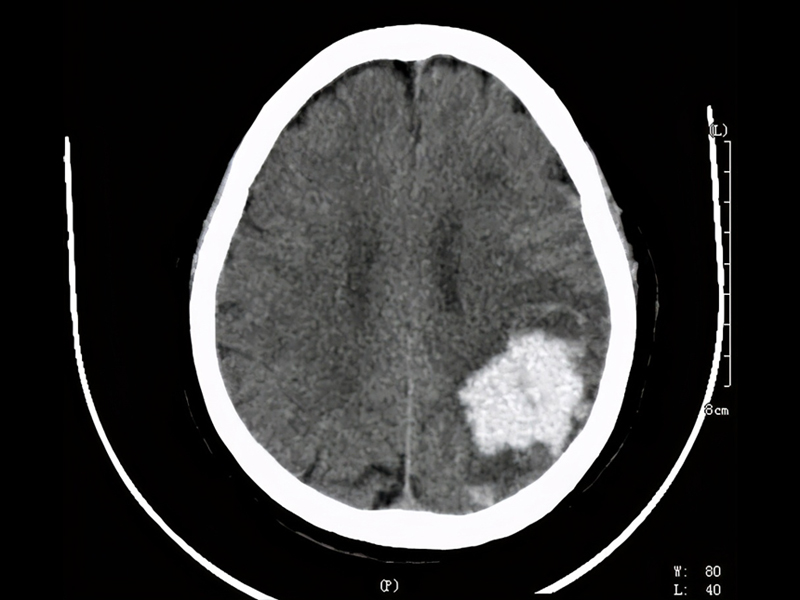

瀏覽:2370 一喝酒就臉紅的人,易患兩種癌症 | 瀏覽:1486 7 點起床 1 點睡覺,腦幹出血 ICU 抢救 | 瀏覽:2155 你的走路姿勢,可能一直都錯了!難看還傷腿! |